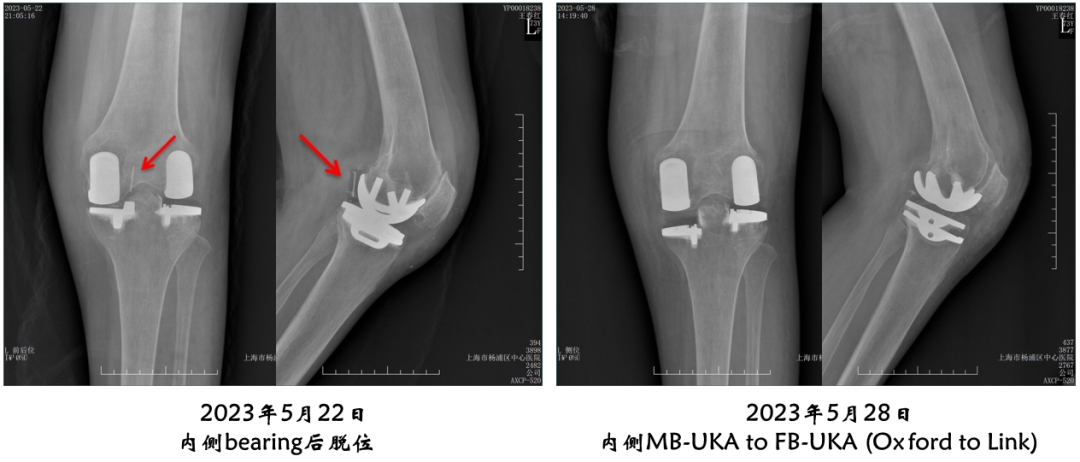

病例4:内侧OxfordUKA术后6.5年外侧进展性OA

病例4:Bi-UKA术后

病例4:Bi-UKA术后Bearing 后脱位的处理